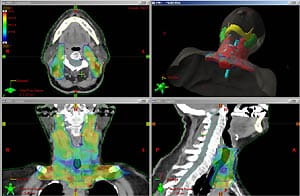

Intensity-modulated radiation therapy (IMRT) gives radiation therapists the ability to "sculpt" the edges of a tumor, minimizing the damage to adjacent healthy tissue. IMRT is an advanced form of radiation therapy used in both cancerous and non-cancerous tumor treatments.

IMRT technology allows the radiation oncologist to deliver radiation to a tumor with more precision and accuracy, resulting in the potential for fewer side effects and higher cure rates.

- Once charted, a physicist uses this data to create a virtual reality simulation to plot your radiation treatment targeting the exact shape of the tumor. An ideal treatment plan can take hours of calculations.

- The linear accelerator delivers radiation beams in about 300 different segments. It focuses the radiation on the tumor, while lessening the dose passing through healthy tissue.